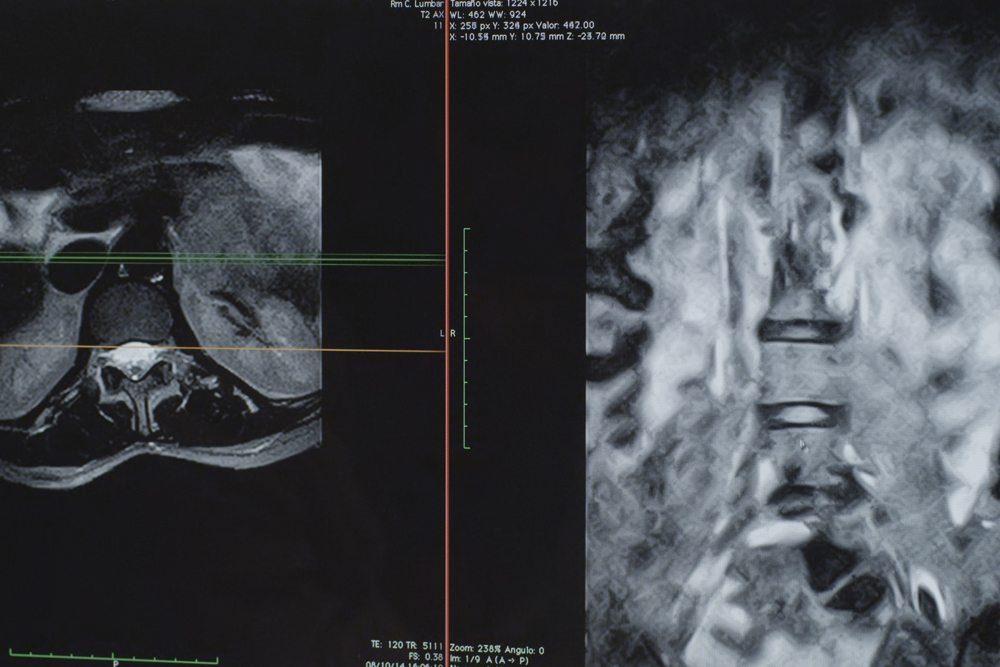

Resonancia Magnética abierta de Alta resolución: 2048 x 2048 pixeles - 256 cortes – 1mm de espesor potencial

Gracias a esta avanzada tecnología de campo magnético permanente, les proporcionamos estudios diagnósticos a 2048 x 2048 píxeles de resolución de imagen, con un alcance potencial de 256 cortes a 1 mm de espesor mínimo. La función de separación de grasa y agua se realiza directamente durante el estudio, al igual que en las resonancias más avanzadas, y el sistema RADAR que posee, corrige los movimientos involuntarios del paciente evitando así errores durante la realización de la prueba. Analizamos el eco de retorno con un avanzado software permitiendo imágenes más nítidas, más estables y de mayor contraste, como la tecnología de predicción y supresión de las corrientes de remolino (ECC system) incorporadas en el propio imán. Con todo ello el potencial de diagnóstico aumenta exponencialmente, permitiéndonos localizar y analizar los artefactos más pequeños que determinada patología pueda originar. Leer más...